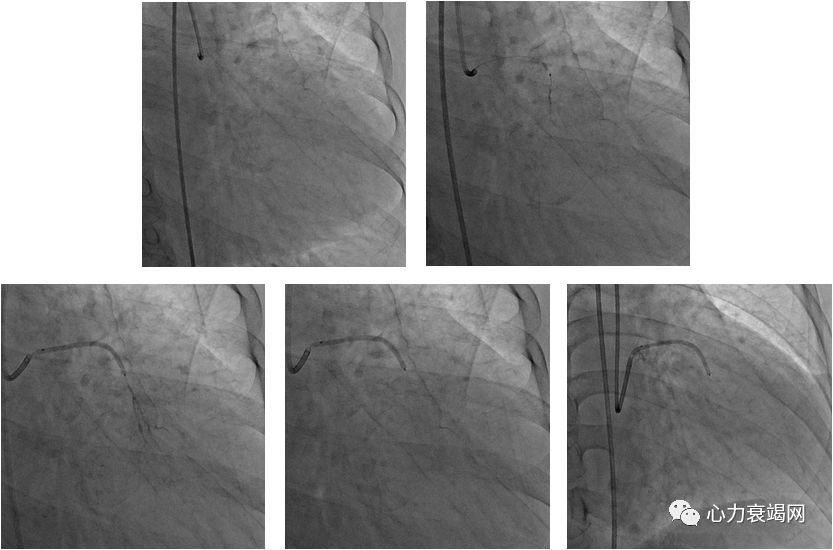

经皮腔内间隔心肌消融术

(PTSMA)

PTSMA由英国医生Sigwart于1991年首次应用于治疗HOCM并取得良好的疗效,随着经验的积累和方法学上的不断改进,该方法日趋成熟,逐渐成为HOCM的主要治疗手段之一

是介入手段,通过导管注入无水酒精,闭塞冠状动脉的间隔支,使其支配的肥厚室间隔心肌缺血、坏死、变薄、收缩力下降,是流出道梗阻消失或减轻。从而改善HOCM患者的临床症状

我科2004-至今,32例PTSMA的病例

特殊病例的HOCM-PTSMA术(case 1)

特殊病例的HOCM-PTSMA术(case 2)

经验

多支消融:谨防泄漏